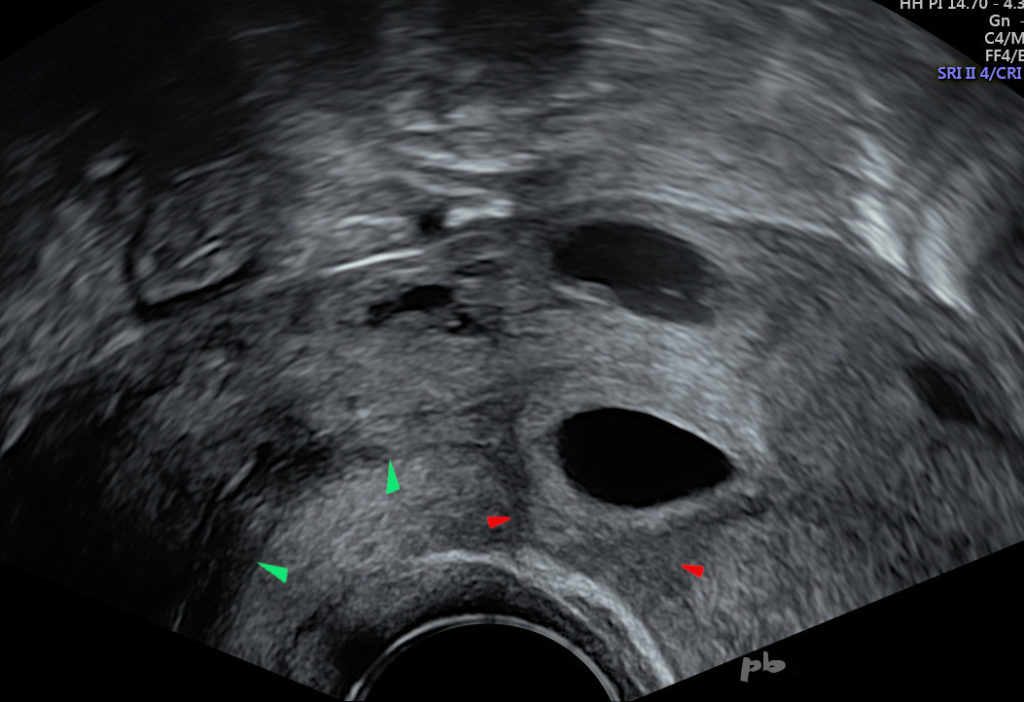

34- GEU interstitielle

- Voie endo-vaginale.

- Grossesse située dans le segment interstitiel de la trompe droite.

- Riche couronne vasculaire venant au contact de la séreuse utérine.

- L’endomètre (★) et la cavité sont bien visibles.

34- Interstitial Ectopic Pregnancy

Transvaginal ultrasonography.

Pregnancy located in the interstitial segment of the right tube.

Rich vascular crown coming into contact with the uterine serosa.

The endometrium (★) and the cavity are clearly visible.